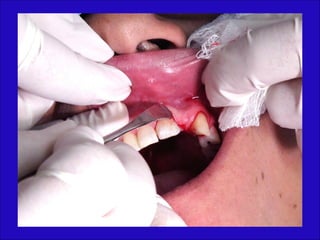

Asepsia y campos

Anestesia de la región

Incisión

Disección cuidadosa del colgajo